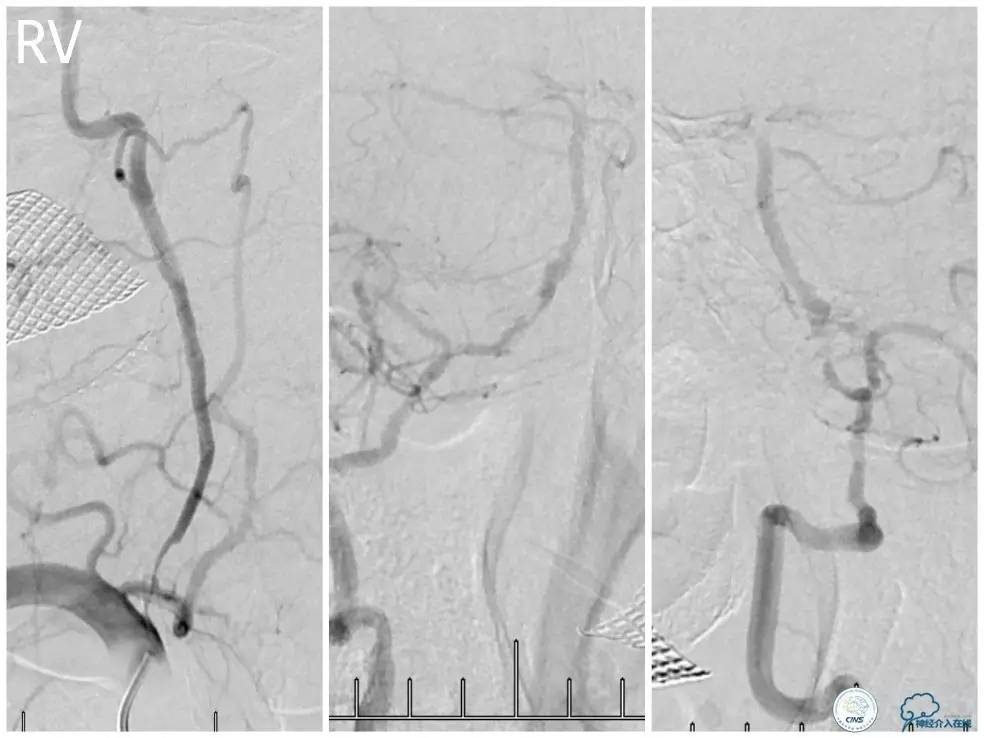

外院DSA(图3):右椎动脉起始处显示不清,右椎动脉V4段重度狭窄,左椎动脉V2-3段经侧支代偿显影。

图3

术前DSA:右椎动脉V1段长段重度狭窄,V4-基底动脉交界区显影浅淡,狭窄程度重,但具体程度显示欠佳(图7)。左椎动脉V1段闭塞,左椎动脉V2远段经侧支代偿显影,V3段以远未见显影(图8)。前循环造影未见明显前循环向后循环代偿(图9)。

图7

图8

图9